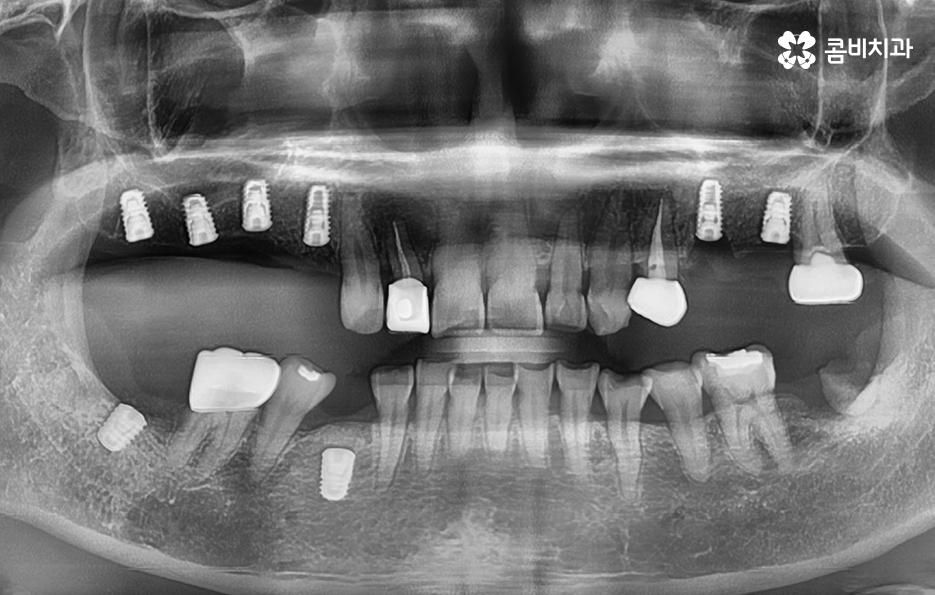

우리가 보편적으로 생각하게 되는 임플란트 치료기간의 경우 치아 하나를 상실하고 임플란트를 1:1로 치료할 때 예상 기간에 대해서 고려하게 되는 경우가 기본적인 접근 방법이라면 실질적으로 치과에서 임플란트를 하게 되는 연령대를 보더라도 보통 50대에서 60대 이후에 치아를 상실하게 되는 환자분들이 급증하기 때문에 위 사진의 사례처럼 여러 치아를 상실하고 임플란트를 식립하게 되는 경우도 많을 거예요

임플란트를 여러개 식립하면 더 오래 걸리나요?

물론 임플란트의 치료 계획에 따라 환자분들의 치료기간도 차이가 있겠지만 보편적으로는 임플란트를 여러개 식립한다고 해서 단순히 더 임플란트의 치료기간이 오래 걸리기 보다는 동시에 임플란트를 식립해도 임플란트 치료기간에서 중요한 골유착 기간은 비슷하기 때문에 식립 개수만큼 치료기간이 비례해서 늘어난다고는 볼 수는 없을 거예요

또는 식립 위치에 따라서 좌, 우 부분적으로 임플란트가 모두 필요한 경우 한 번에 모두 식립을 할 경우 식사가 제한이 되기 때문에 한 쪽 먼저 치료하고 반대쪽을 치료하는 경우가 많아 총 기간은 치료 계획에 따라 차이가 있을 수 있어요.